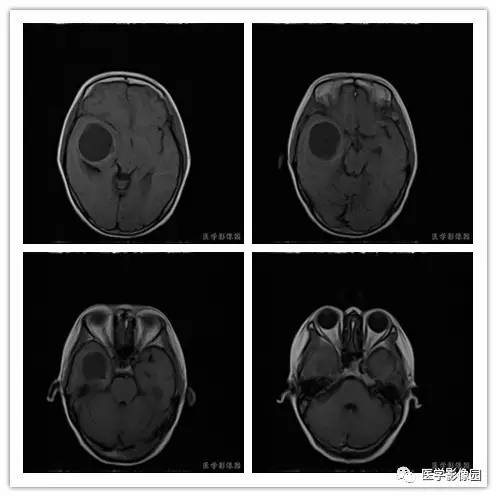

影像学表现:右侧颞叶深部区见一长T1、长T2囊样信号,成明显环形强化、未见明确结节影,没有FLAIR和DWI图,内见分隔,边界较清,周围水肿不明显,右侧脑室明显受压、颞角扩大,右侧脑沟明显变浅,脑中线结果向左偏移。

结果 血管外皮细胞瘤

血管外皮细胞瘤好发于颅底、矢状窦或大脑镰旁、小脑幕等硬脑膜或静脉窦附近。肿瘤多呈分叶形或不规则形,少数可呈椭圆形或扁圆形。多数具有脑外肿瘤特点,与脑膜或大脑镰和小脑幕有广基底连接,少数与脑膜以窄基底连接,后都可能是由于肿瘤生长时间短而又生长体积较大。

1.肿瘤主要表现为等长T1 、等长T2 混杂信号影,偶可见短T1 或短T2 信号影,注药后,肿瘤增强明显但不均匀;

2.外形呈不规则分叶状;

3.半数以上的肿瘤与硬膜窄基底相连;

4.肿瘤内常可见血管流空影而见不到钙化影;

5.肿瘤附近骨质可见破坏而见不到增生硬化。